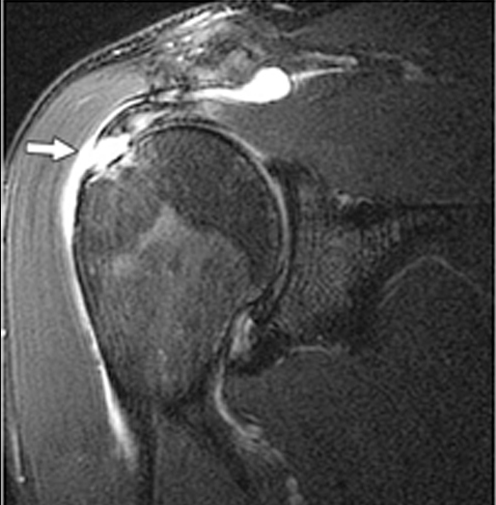

Η διάγνωση βασίζεται σε κλινική εξέταση και απεικονιστικό έλεγχο, όπως μαγνητική τομογραφία (MRI) ή υπερηχογράφημα.